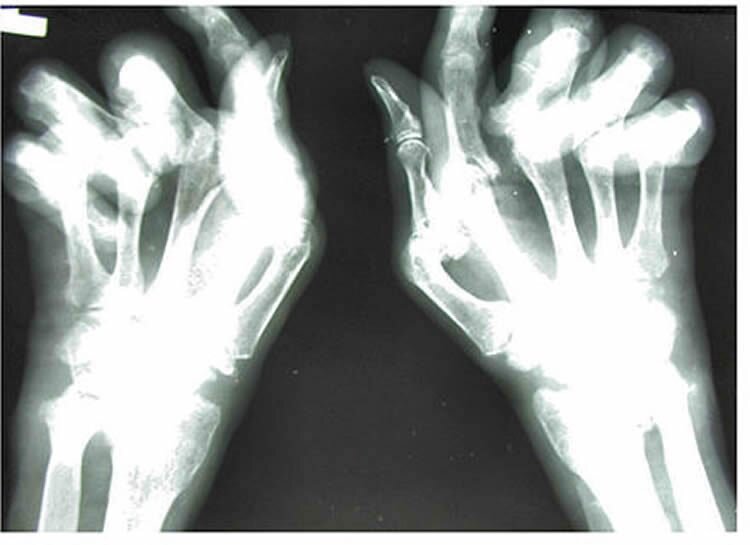

«Ревматоидный артрит — это воспалительное аутоиммунное состояние, для которого характерны неприятные уровни воспаления, влияющие на суставы человека и другие части тела, вызывая усталость, сонливость и когнитивные дисфункции. Несмотря на предположения, что воспаление, которое мы видим в крови, влияет на мозг, до этого исследования мы не знали точно, где и как происходят изменения в мозге», — говорит доктор Эндрю Шрепф, один из ведущих авторов исследования.

Басу, будучи практикующим ревматологом, отмечает — развитие противовоспалительной терапии за последние десять лет позволило уменьшить периферическое воспаление, которое приводит к боли в суставах и недееспособности при ревматоидном артрите. Однако больные продолжают жаловаться на усталость и плохое самочувствие.